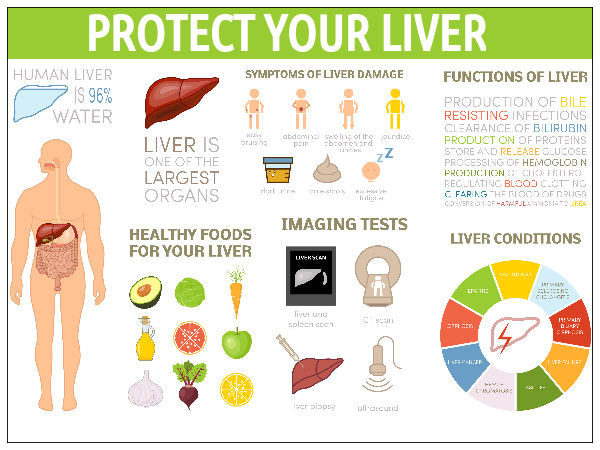

How To Improve Liver Function Boldsky

Liver Health 5 Superb Foods That Helps To Boost Liver Function

Liver Health 5 Superb Foods That Helps To Boost Liver Function